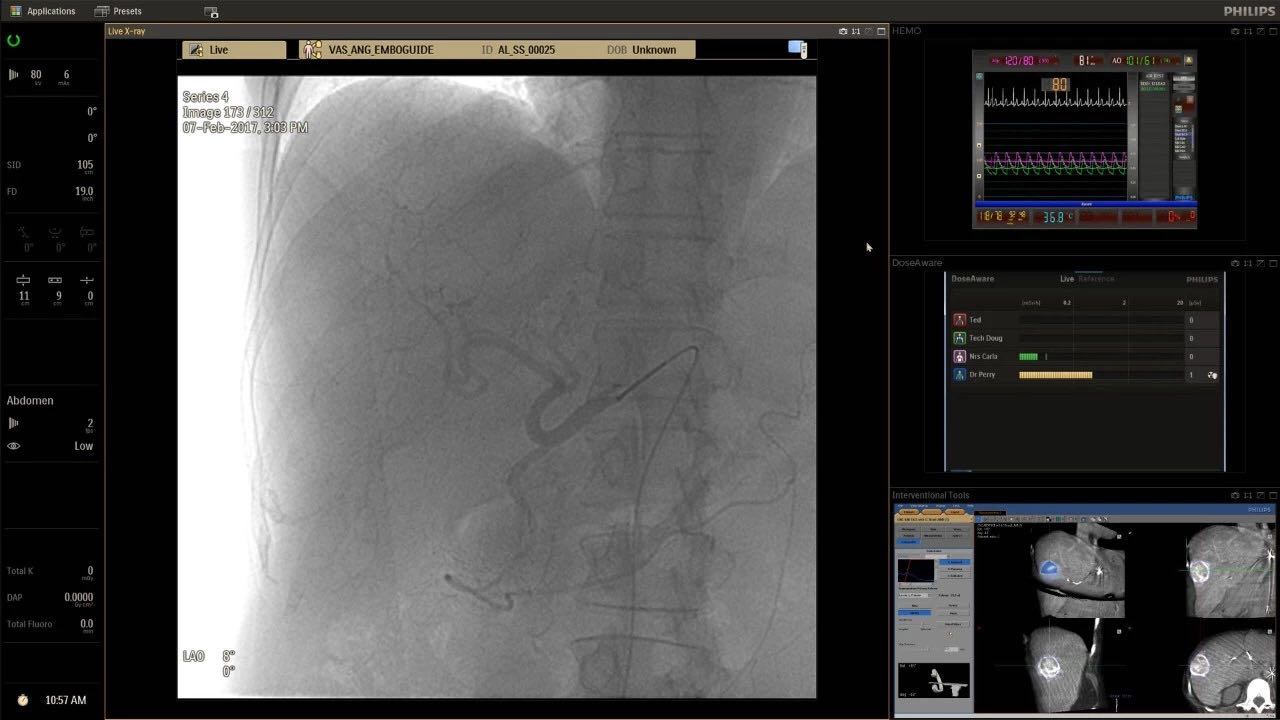

在日益復(fù)雜的干預(yù)期間,臨床醫(yī)生需要快速、輕松地可視化關(guān)鍵解剖結(jié)構(gòu)并確定手術(shù)過(guò)程中患者的變化。2019年1月17日,飛利浦宣布推出采用FlexArm的Azurion 7 C20,旨在提高圖像引導(dǎo)程序的定位靈活性。

帶有FlexArm的Azurion 7 C20 包含一系列創(chuàng)新技術(shù),使臨床醫(yī)生可以更輕松地在整個(gè)患者身上進(jìn)行二維和三維成像。當(dāng)臨床醫(yī)生移動(dòng)系統(tǒng)時(shí),圖像光束自動(dòng)保持與患者的對(duì)準(zhǔn),允許更一致的可視化并使他們能夠?qū)⒆⒁饬性谥委熒稀?/span>

飛利浦表示,采用FlexArm設(shè)計(jì)的Azurion 7 C20可提供卓越的靈活性和直觀的控制。該系統(tǒng)由智能運(yùn)動(dòng)引擎驅(qū)動(dòng),可在八個(gè)不同的軸上移動(dòng),所有這些軸均由其單個(gè)“Axsys”控制器控制。臨床醫(yī)生的模擬測(cè)試表明,該系統(tǒng)有可能顯著減少患者,工作人員和設(shè)備的重新定位,從而改善微創(chuàng)手術(shù)的可及性,包括通過(guò)患者手腕進(jìn)入身體的手術(shù)(橈動(dòng)脈入路),并降低患者的風(fēng)險(xiǎn)。無(wú)意中拔出電線和管子,以及節(jié)省大量時(shí)間。該系統(tǒng)非常適合混合手術(shù)室(OR),可滿足一個(gè)房間內(nèi)的多種專業(yè)需求,例如手術(shù)和血管內(nèi)手術(shù)的組合。

(FlexArm在不少于8軸的情況下旋轉(zhuǎn),從而創(chuàng)建幾乎無(wú)限的靈活性來(lái)執(zhí)行成像,從頭部到腳部在左側(cè)和右側(cè)進(jìn)行2D和3D可視化。圖像光束保持與患者對(duì)齊,允許在旋轉(zhuǎn)或角度期間更好地可視化解剖結(jié)構(gòu)。使用Axsys運(yùn)動(dòng)控制系統(tǒng)輕松操作支架。)